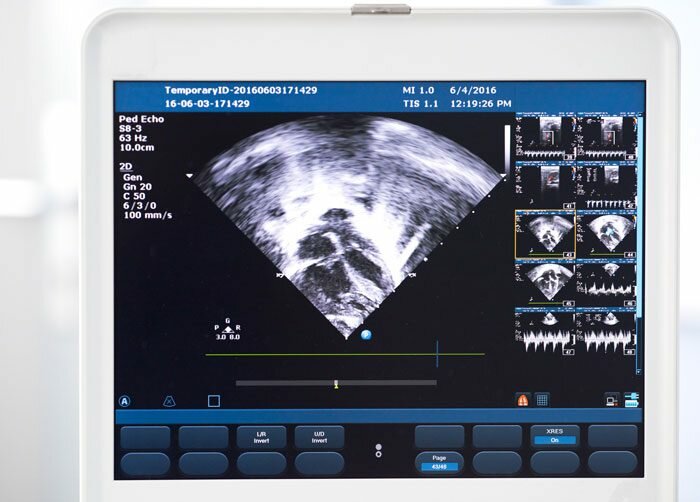

Echocardiograms: High-frequency sound waves create images of a patient's heart. Resting echoes and stress echoes are performed to evaluate the function of a patient's heart.

St. Margaret’s Health offers 2D, 3D and 4D sonography options.